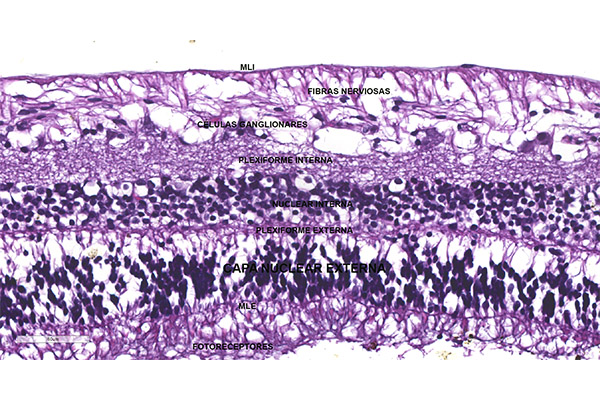

Capa nuclear externa

La capa nuclear externa está formada por ocho o nueve capas de células con núcleo densamente teñido. Según la morfología nuclear podemos distinguir dos tipos de células: una más pequeña y de núcleo más densamente teñido que corresponden a los bastones y de unas más grandes y de núcleo más débilmente teñido, las cuales tienden a ubicarse justamente por dentro de la membrana limitantes externa pertenecientes a los conos. Encontramos dendritas que se extienden desde ambos tipos de células hacia la capa plexiforme externa. Ocasionalmente los núcleos de los conos se encuentran desplazados dentro de la capa de conos y bastones como una variación normal.

- Categoría de la entrada:Anatomía e histología / Retina